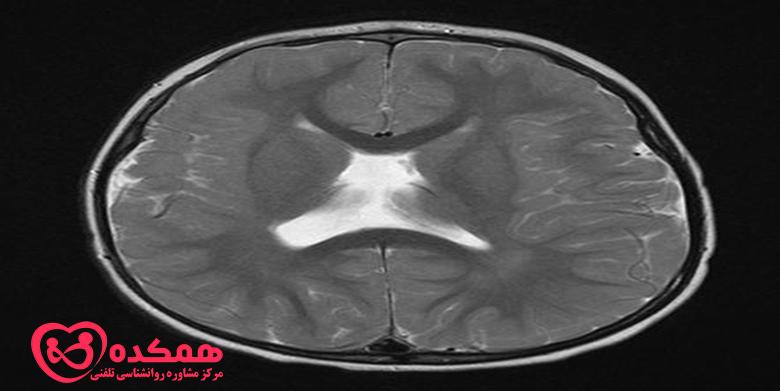

این نوع شدیدتر دیسپلازی قشر مغز است که در آن سلولهای مغزی علاوه بر آرایش غیرطبیعی سلولها، غیرعادی به نظر میرسند. این نوع بیشتر در کودکان دیده می شود و هر دو قسمت گیجگاهی و پیشانی مغز را درگیر می کند. معمولاً در تصویربرداری رزونانس مغناطیسی (MRI) دیده می شود.

پزشک شما تشخیص صرع را بر اساس سلامت فرزندتان، سابقه پزشکی گذشته و سابقه خانواده شما انجام می دهد. آن ها همچنین یک معاینه فیزیکی دقیق انجام می دهند. و سعی می کنند تا آن جا که می توانند از شما در مورد تشنج های فرزندتان یاد بگیرند. آن ها همچنین ممکن است آزمایش خون انجام دهند. اگر پزشک مشکوک به دیسپلازی قشر مغز باشد، آزمایشات بیشتری تجویز خواهد شد. این ها شامل الکتروانسفالوگرام (EEG) و تصویربرداری رزونانس مغناطیسی (MRI) است.

اگر MRI نرمال باشد، پزشک آزمایشهای تصویربرداری دیگری مانند اسکن توموگرافی گسیل پوزیترون (PET)، SISCOM یا مگنتوآنسفالوگرافی (MEG) را برای تعیین محل وقوع تشنج تجویز میکند. دیسپلازی کانونی کورتیکال به ندرت در سی تی اسکن قابل مشاهده است و گاهی در MRI نیز غیرقابل تشخیص باقی می ماند. در موارد دیگر، ناحیه آسیب دیده که در اسکن MRI نشان داده میشود. در واقع میتواند بزرگتر از چیزی باشد که توسط MRI نشان داده میشود. این می تواند بر نتایج جراحی تاثیر بگذارد.

تست های مختلف تصویر برداری برای دیسپلازی قشر مغز

به همین دلیل، پزشکان از سایر تستهای تصویربرداری قدرتمند مانند ترکیب MRI با وضوح بالا و تست FDG-PET برای شناسایی دیسپلازی قشر مغز استفاده میکنند. تمرکز اصلی درمان دیسپلازی قشر مغز، کنترل تشنج است.